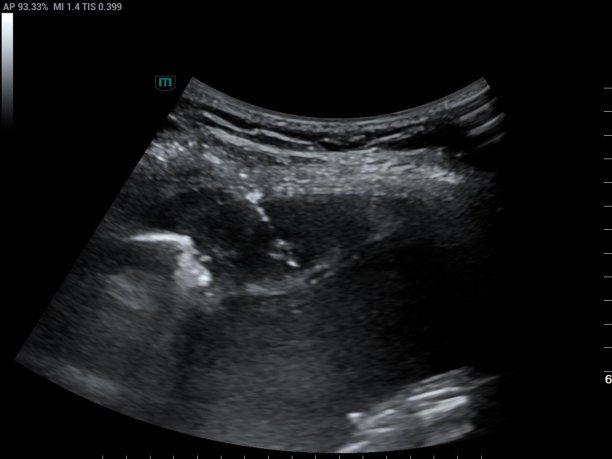

超声医学科主任潘国栋与主治医师刘金昊依据超声显示的病变范围,细致规划了穿刺点、进针路线及深度,避开了肋间动脉、神经及病变侧方的肺组织。全程在超声的实时引导下,穿刺针精准到达病变部位,采集了2条病变组织。

经超声引导下避开血管、实时显示穿刺针从进入胸膜结节到击发穿刺针的全过程

术后经病理科会诊,提示:穿刺组织呈慢性肉芽肿性炎,并见个别抗酸染色阳性的杆菌,结合分子检测结果,符合结核分枝杆菌感染。特殊染色:抗酸染色(+)。患者结核性胸膜炎诊断明确。